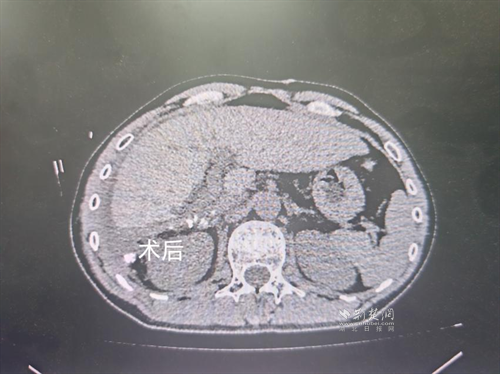

經(jīng)過肝膽外科牽頭組織的多學(xué)科MDT會診,團(tuán)隊(duì)確認(rèn)其適合接受當(dāng)前國際先進(jìn)的釔90樹脂微球選擇性內(nèi)放射治療。治療僅一個月后,患者病灶即從10cm縮小至6cm;術(shù)后六個月復(fù)查顯示,病灶體積進(jìn)一步縮小近40%,影像學(xué)檢查提示完全緩解,臨床分期成功轉(zhuǎn)化,達(dá)到手術(shù)切除標(biāo)準(zhǔn)。